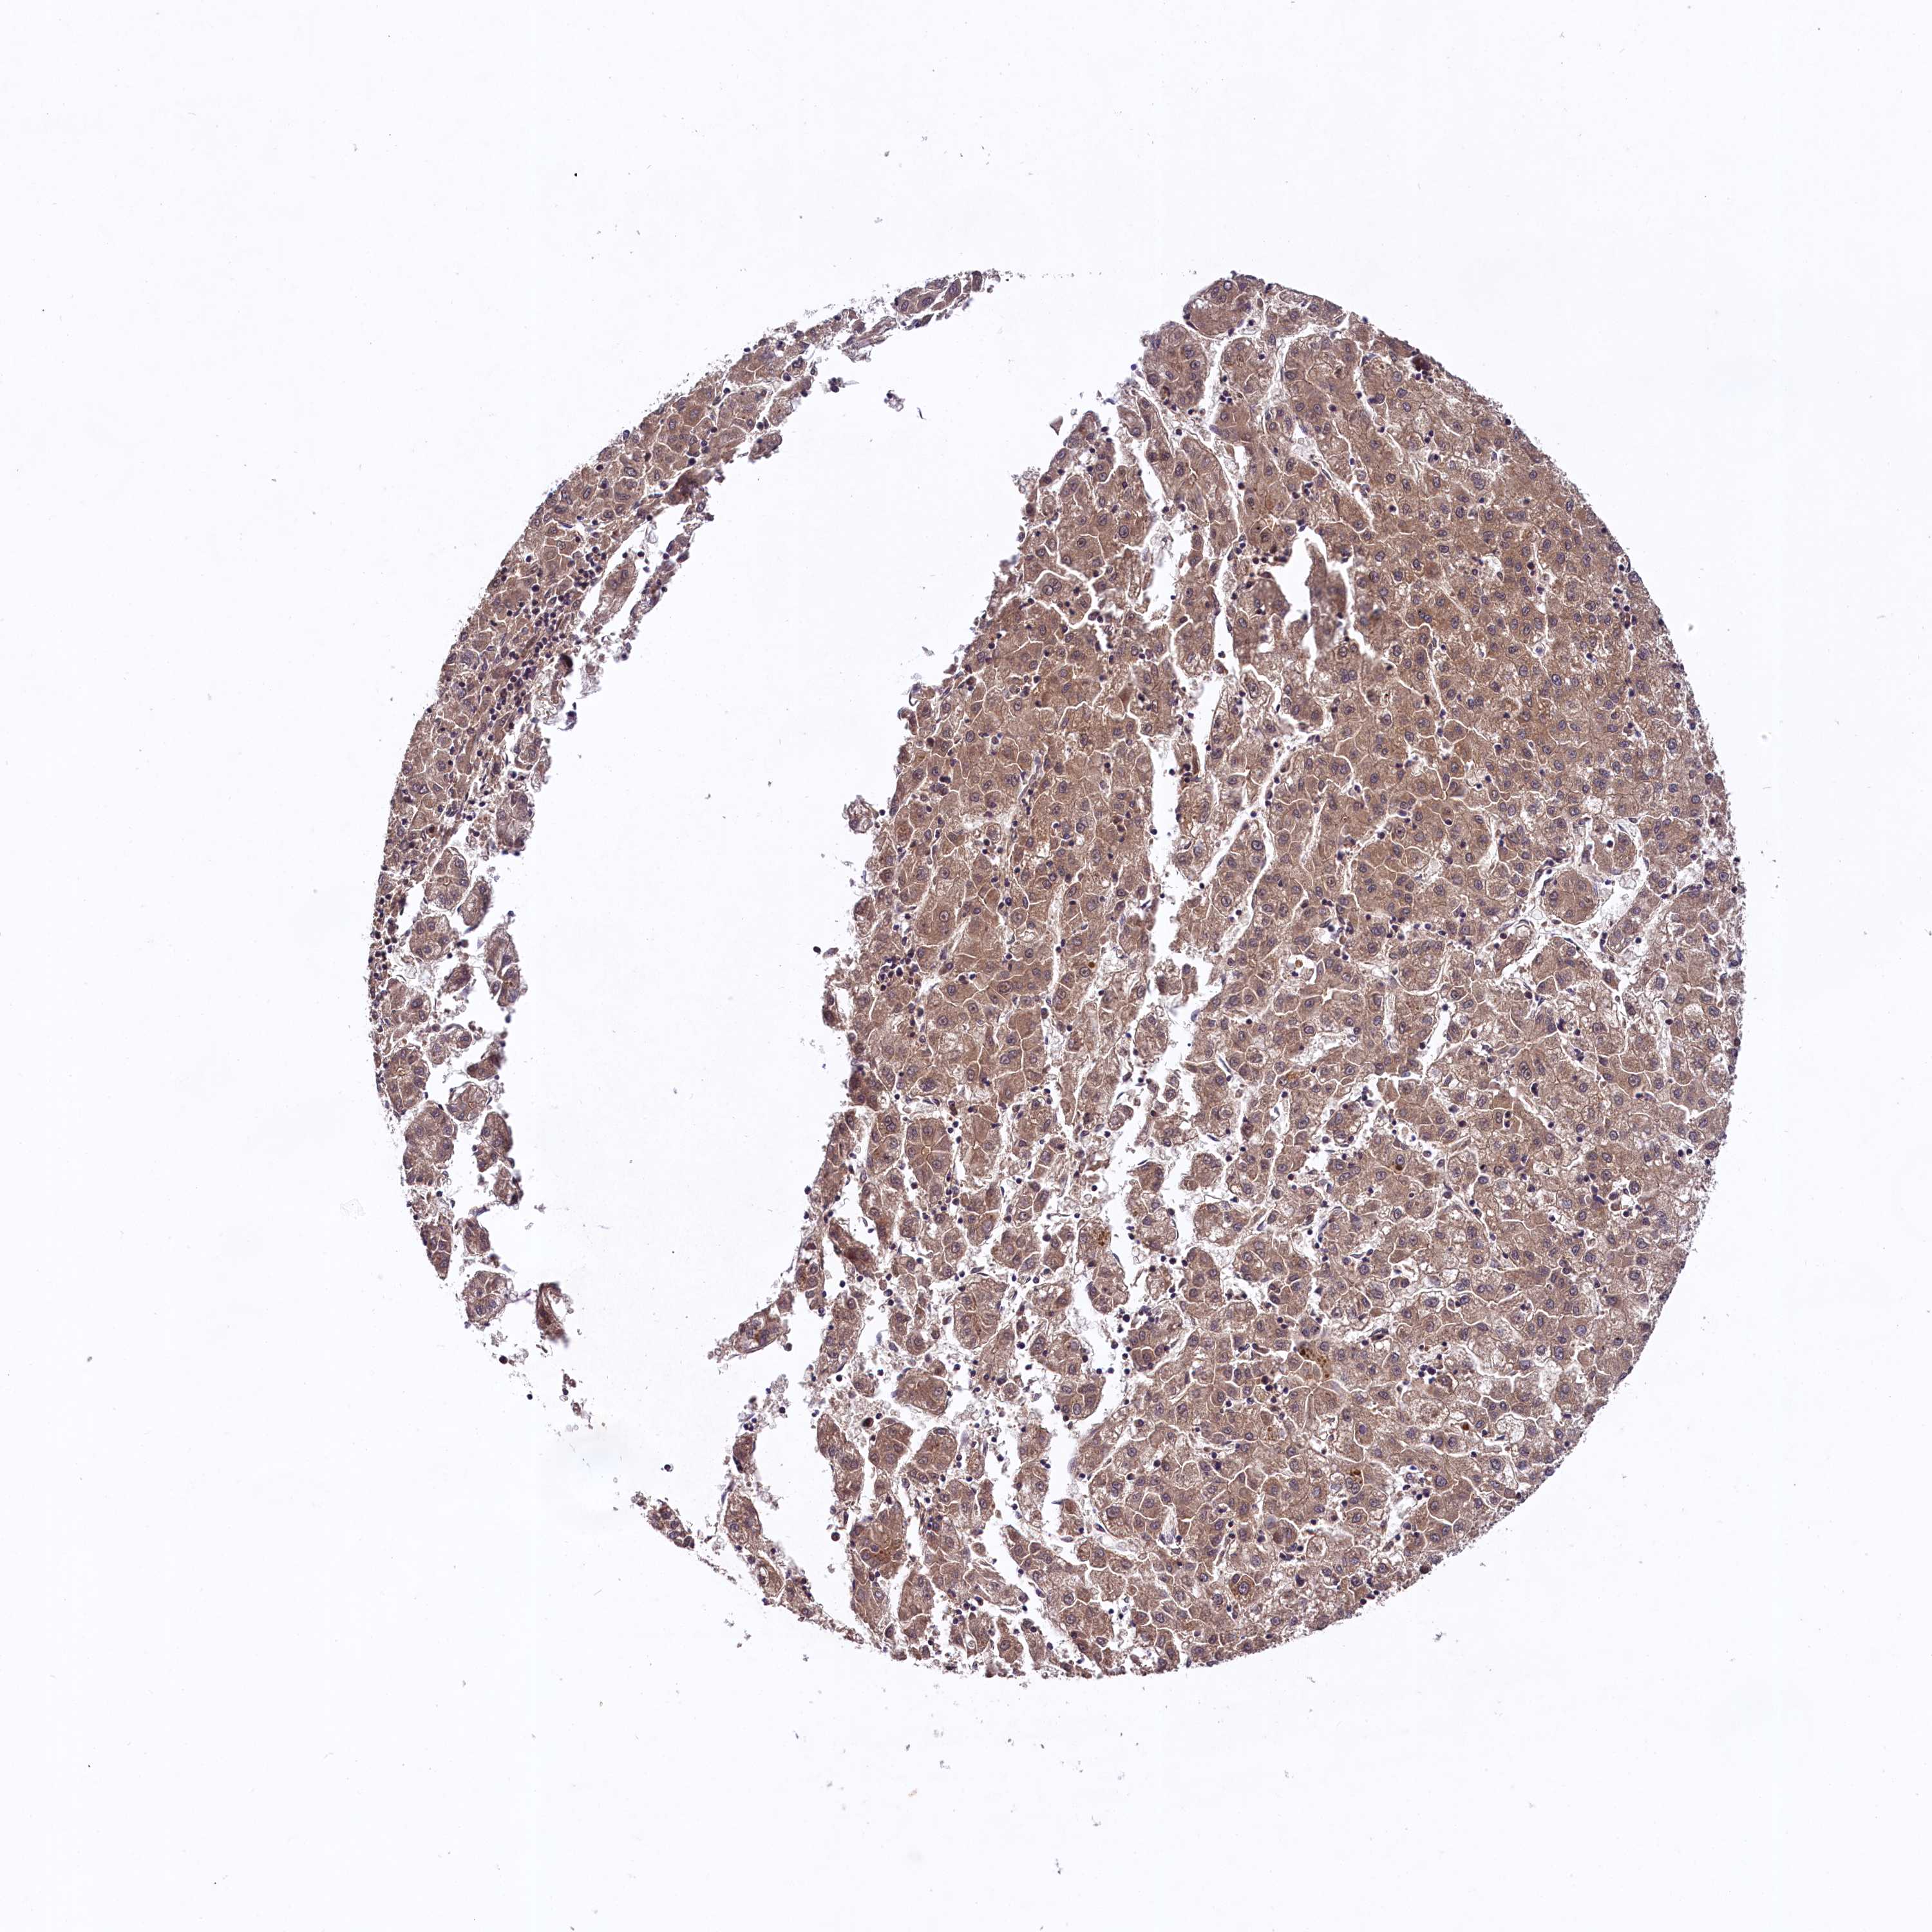

LIVER CANCER - Protein expressioni

A mouse-over function shows sample information and annotation data. Click on an image to view it in a full screen mode. Samples can be filtered based on level of antibody staining by selecting one or several of the following categories: high, medium, low and not detected. The assay and annotation is described here.

Antibody stainingi

Antibody staining in the annotated cell types in the current human tissue is reported as not detected, low, medium, or high, based on conventional immunohistochemistry profiling in selected tissues. This score is based on the combination of the staining intensity and fraction of stained cells.

Each image is clickable and will lead to virtual microscopy that enables deeper exploration of all samples and also displays staining intensity scores, fraction scores and subcellular localization as well as patient and tissue information for each sample.

Antibody HPA041953

Staining

High

Medium

Low

Not detected

Intensity

Strong

Moderate

Weak

Negative

Quantity

>75%

75%-25%

<25%

None

Location

Nuclear

Cytoplasmic/membranous

Cytoplasmic/membranous,nuclear

Cholangiocarcinoma

Carcinoma, Hepatocellular, NOS